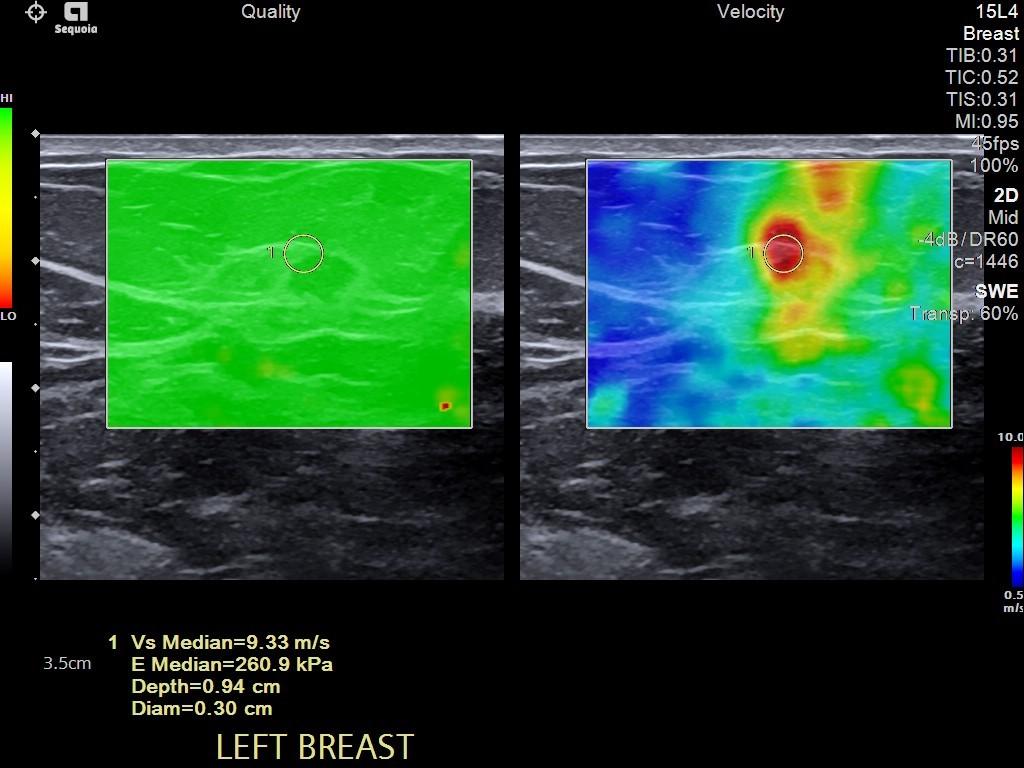

Detect cancer like never before: See the stark difference between a stiff lesion and breast tissue to mitigate false negatives and avoid unnecessary biopsies with our proprietary, next-generation 2D Shear Wave Elastography algorithm